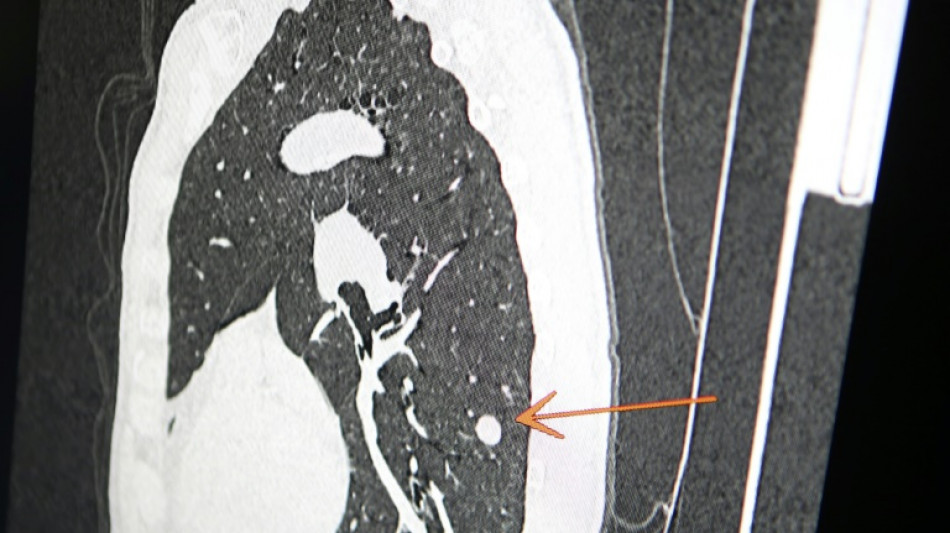

Una clínica del norte de Inglaterra dio un gran susto a cientos de pacientes al enviar el mensaje "diagnóstico: cáncer de pulmón agresivo con metástasis" en lugar de sus buenos deseos de Navidad, informó el diario The Sun el jueves.

El 23 de diciembre a las 15H49, los pacientes de este centro de salud de Askern, cerca de la ciudad de Doncaster, recibieron un mensaje de texto en su teléfono informándoles de este diagnóstico, pidiéndoles que rellenaran los formularios correspondientes y concluyendo: "Gracias".

Según The Sun, entre los destinatarios del mensaje figuraba Chris Reed, un padre de familia de 57 años, que esperaba resultados de análisis para determinar si padecía cáncer de pulmón.